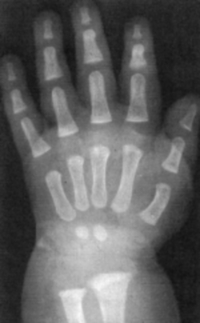

Sexo Masculino

Recém-Nascido

idade óssea - RN